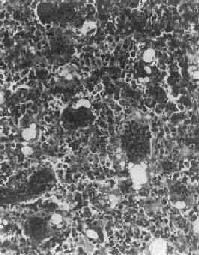

图17-5 骨巨细胞瘤 肿瘤位于肱骨上端,骨皮质破坏,有病理性骨折 镜下,肿瘤主要由单核基质细胞及多核巨细胞等两种细胞组成(图17-6),间质血管丰富。基质细胞为梭形、卵圆形或圆形,细胞境界不清楚,常见胞浆突起。细胞核较大,染色质量中等,可具有一个核仁。多核巨细胞常较均匀地散布在基质细胞之间,是为本瘤的特点。多核巨细胞的直径常为30~60μm,核数一般为15~20个,最多可达100个以上,常聚集在细胞的中央。核的形态与单核基质细胞相似。细胞边界不规则,但分界较清楚,胞浆丰富,略呈嗜碱性,有时还可见含大量脂类的泡沫细胞。本瘤间质血管丰富,有多少不等的胶原纤维。肿瘤本身无成骨现象,但有时见有类骨组织及新生骨小梁,常见于纤维组织的周围,可能是一种反应性新骨形成或病理性骨折后形成的骨痂。

图17-6 骨巨细胞瘤(Ⅰ级) 肿瘤由大量基质细胞和多核巨细胞两种细胞组成 【病理分级】 骨巨细胞瘤在病理组织学上,根据基质细胞和多核巨细胞的数量及异型性的程度分为三级:基质细胞分化好,形态大小一致,偶见核分裂像。多核巨细胞数量多、体积大、细胞核多者为Ⅰ级;基质细胞分化差,异型性明显,细胞密度高,核分裂像多,具有肉瘤样改变。多核巨细胞数量少、体积小、细胞核也少,有明显的异型性者为Ⅲ级;介于两者之间者为Ⅱ级。Ⅰ级基本为良性,具低度侵袭性,刮除术后可复发。多次复发后可变为恶性。Ⅲ级呈恶性肿瘤的表现,易复发和转移至肺。病理分级对判断骨巨细胞瘤的良恶性程度和预后以及治疗方法的选择有一定的参考价值,但并非绝对可靠。 【临床病理联系】 早期症状是局部疼痛及压痛,疼痛性质可为间歇性。位于浅表部位者,可出现局部肿胀或肿块。当肿瘤增大而使表面骨皮质膨胀变薄时,触之有捏乒乓球样感觉。位于脊椎的肿瘤,可引起相应神经压迫症状。 (四)骨肉瘤 骨肉瘤(osteosarcoma)是指肿瘤细胞能直接形成肿瘤性类骨组织或骨组织的恶性肿瘤。骨肉瘤是原发性骨恶性肿瘤中最常见者,约占骨恶性肿瘤的1/3。骨肉瘤的发病率在男性略高,可发生于各级年龄,但最多见于11~20岁,其次为21~30岁,年龄越大,发病率越低。骨肉瘤多发生在骨骼生长发育的旺盛时期,其恶性程度又较高,因此是严重影响劳动生产力并危及生命的重要肿瘤之一,早期诊断及早期治疗具有特别重要意义。 【病因】 骨肉瘤病因不明,其发生与下列因素有关。①骨骼的活跃生长。②放射线:实验证明凡能在骨骼内积存的放射性物质均可诱发骨肉瘤;某些骨疾患如骨巨细胞瘤、动脉瘤性骨囊肿或骨外肿瘤如乳腺瘤、视网膜母细胞瘤等的局部放射线照射治疗,偶尔可引起继发性骨肉瘤。③遗传:视网膜母细胞瘤基因(Rb基因,位于染色体13q14,目前已知它是一种抑癌基因)突变或缺失的遗传性视网膜母细胞瘤患者,发生骨肉瘤的危险性远远高于一般人。近年发现一些骨肉瘤患者也有Rb基因的突变。④病毒:实验证明,动物的骨肉瘤与病毒感染有关,但对人类骨肉瘤尚未有确切的材料说明与病毒的关系。⑤良性骨疾患的恶变:如多发性骨软骨瘤、骨Paget病、骨纤维结构不良等可恶变而发生骨肉瘤,亦称为继发性骨肉瘤。 【病理变化】 骨肉瘤可发生于任何骨,最常见于四肢长骨,半数以上发生于股骨的下端及胫骨或腓骨的上端,其次为肱骨上端。颌骨、脊椎骨、肩胛骨和髂骨等较少见。长骨的骨肉瘤发病年龄较小,发生于扁骨者年龄较大。大多数骨肉瘤发生于骨的内部或中央,在长骨位于干骺端,肿瘤在骨髓腔内及向周围骨皮质浸润形成肿块。因骨骺软骨对骨肉瘤的浸润具有一定的抵抗力,在骨骺板闭合骨化之前(约17~20岁),一般不侵及骨骺端。少数骨肉瘤发生于骨表面,称为皮质旁骨肉瘤,其临床、X线和病理表现均与一般骨肉瘤不同。 肉眼观,长骨肿瘤位于干骺端的骨髓腔中央或为偏心性。一侧或四周的骨皮质被浸润和破坏,其表面的骨外膜常被掀起。在切面上可见肿瘤上、下两端的骨皮质和掀起的骨外膜之间形成三角形隆起,其间堆积由骨外膜产生的新生骨。此三角称为Codman三角,这在X线照片中可以显示出来。在骨外膜被掀起时,自骨外膜通往骨皮质的小血管因受到牵拉而呈垂直于骨皮质分布,在这些垂直的小血管周围,组织的血液供应丰富,故新骨形成增多,这些反应性新生骨小梁呈放射状与骨表面垂直分布(图17-7),在X线上表现为日光放射状阴影,这种现象与上述Codman三角在X线上对骨肉瘤的诊断具有特征性。